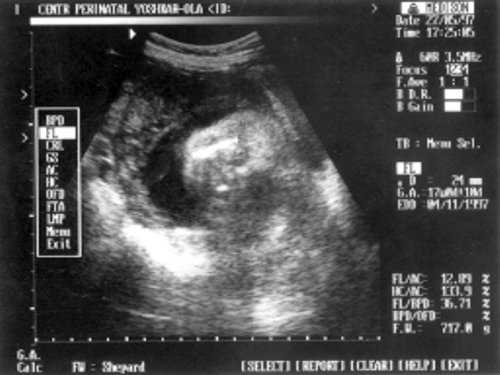

Данные фетометрии:

- (бипатериальный размер головы - от виска до виска) = 65 мм - 26 нед.,

- ОкГ (окружность головы) = 244 - 26 нед. + 3 дня.

- МРМ (межполушарный размер мозжечка) = 25,6 мм - 23,5-24 нед. (рис. 1)

- ОкГрК (окружность грудной клетки) = 42 мм - 19,5 нед.

- ОЖ (окружность живота) = 182 мм - 22 нед. + 6 дн.

- ДБ (длина бедра) = 24 мм - 17 нед. (рис. 2)

- Плечевая кость = 16 мм - 14,5 нед. (рис. 3)

- Кости предплечья = 17,5 мм - 15,5 нед. (рис. 4)

- Малая берцовая кость = 22 мм - 18,5 нед.

- Большая берцовая кость = 24 мм - 18,5 нед.

Рис. 1. УЗИ плода - голова.

Рис. 2. УЗИ плода - бедро.

Рис. 3. УЗИ плода - плечевая кость.

Рис. 4. УЗИ плода - кости предплечья.